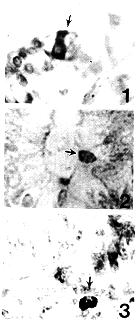

12周胎儿阑尾内未见到IAPP-IR细胞,14周可见很少单个分散的IAPP-IR细胞分布于阑尾粘膜上皮中。15~38周,各胎龄组均有多例于粘膜表面上皮及腺上皮中见到单个、分散的IAPP-IR细胞,胞体多呈圆形、卵圆形,也有的呈柱状或锥形,胎期阑尾中IAPP-IR细胞的共同特点为细胞胞体较小,均近上皮游离端分布(图1,2)。据此,我们推测IAPP-IR细胞是否如同绒毛顶端具有感觉-内分泌作用的濑木帽[3]一样,具有感受肠腔信息的功能?但对此尚需进一步探讨。可偶见位于固有膜中的IAPP-IR细胞(图3)。在胎期阑尾,IAPP-IR细胞从数量、形态到免疫染色强度均未见明显变化。

图1 16周胎儿阑尾,↑示位于上皮近游离端呈柱状的IAPP-IR细胞 ×268

图2 18周胎儿阑尾,↑示单个位于腺上皮近游离端的IAPP-IR细胞 ×268

图3 16周胎儿阑尾,↑示位于固有层内的IAPP-IR细胞 ×268

Fig.1 The appendix at week 16 of gestation,↑showing a columnar IAPP-IR cell located near the free border of epithelium. ×268

Fig.2 The appendix at week 18 of gestation,↑showing a IAPP-IR cell located near the free border of glandular epithelium. ×268

Fig.3 The appendix at week 16 of gestation,↑showing a IAPP-IR cell located in the lamina propria. ×268